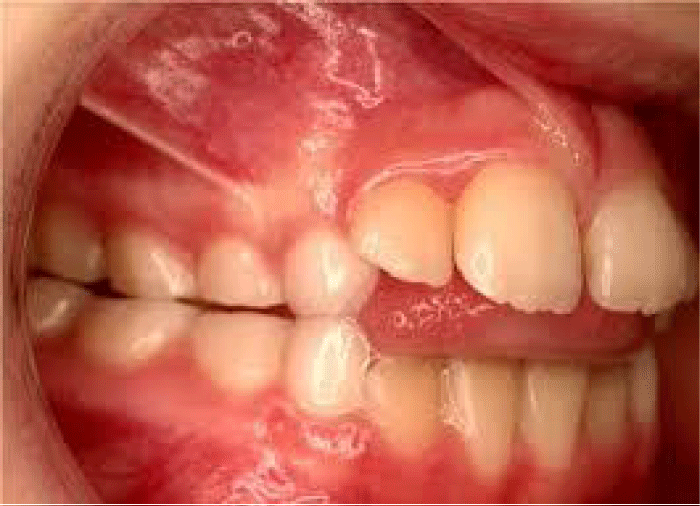

后打开咬

后打开咬之间的联系可以被定义为失败后牙齿的牙齿咬合时中心闭塞(图2)。

在图2中我们可以看到,之间没有阻塞上颌和下颌前磨牙。上颌和下颌磨牙有轻微的接触。前希望和覆咬合是正常的。